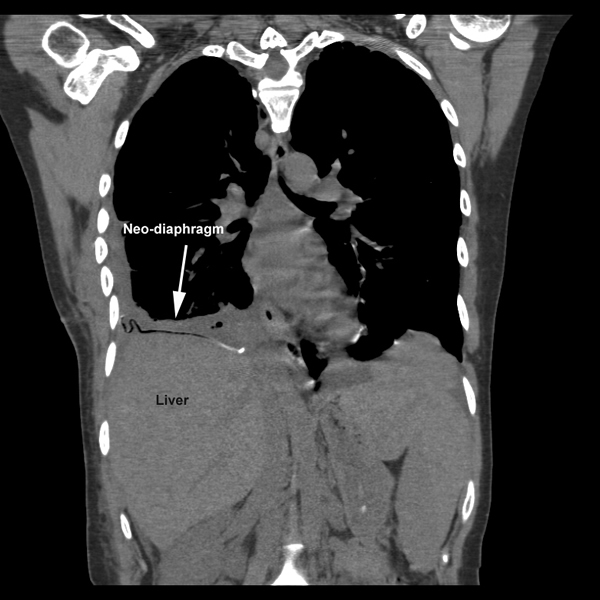

Figure 8: Postoperative chest CT scan reveals neo-diaphragm and reduction of the liver back into the abdomen. |

She made an uneventful recovery and was discharged on postoperative day seven. Pathologic examination of the liver revealed normal liver parenchyma with no diagnostic abnormality. The visceral and parietal pleural biopsies revealed chronic pleuritis. A postoperative CT scan revealed an intact diaphragmatic repair with the liver within the abdomen and the right lower lobe completely expanded (Figure 8). Patient has been seen in our clinic approximately 3 months following surgery with no recurrence of hepatic herniation, improved effort tolerance and no recurrence of her loculated effusion.